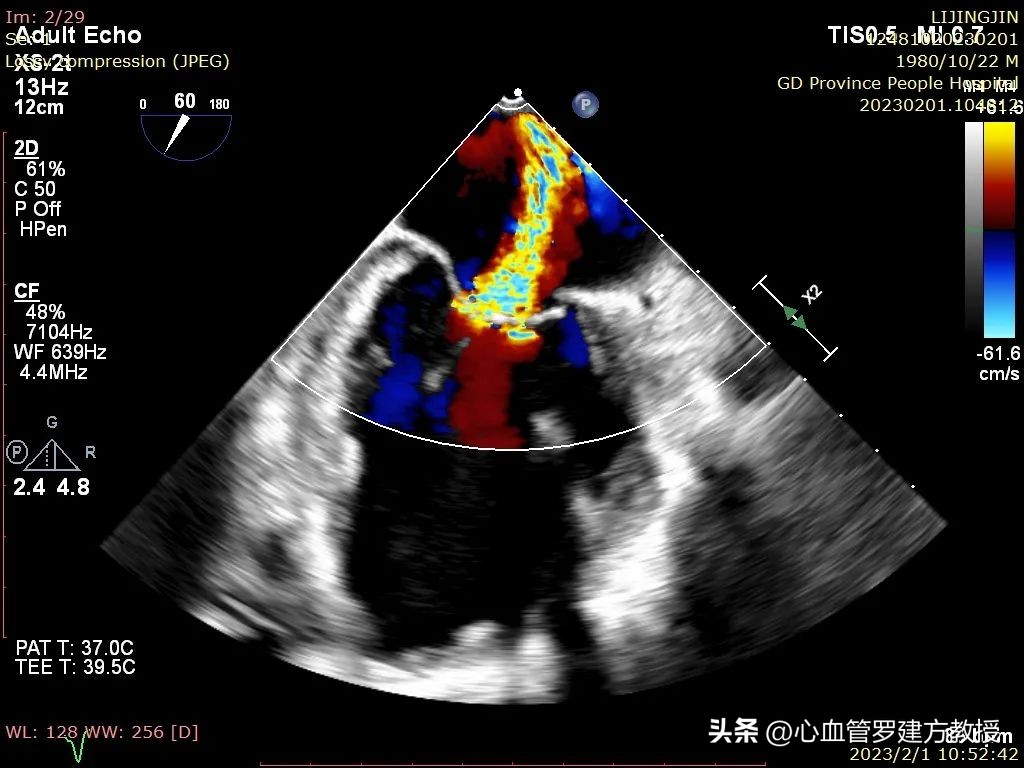

术前超声图

患者为功能性二尖瓣反流(FMR)Type IIIb基线期MR3+;二尖瓣叶;PML=1.17cm、AML=2.77cm反流束宽度=11.7mm反流位于2区;